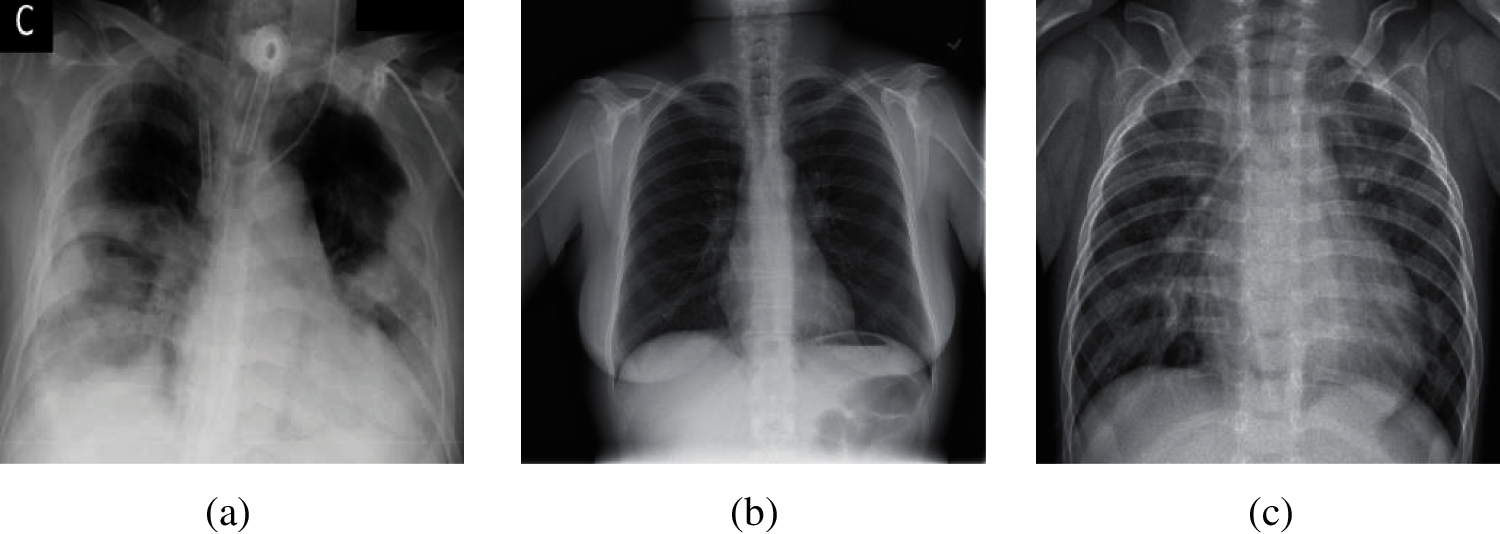

The current diagnostic methods of COVID-19 are: (i) nucleic acid testing. This method needs a long time from sample collection to publish test results, which requires high requirements on the sample testing environment. In addition, samples are vulnerable to contamination; hence, this method has the possibility of sampling failure, which needs to repeat the collection operation [5]. (ii) chest computed tomography (CCT). The cost of this method is high, and there is some radiation in the scan process of computed tomography. In addition, for lesions with a density similar to normal tissues, which are easy to miss by plain scanning [6]. (iii) chest X-ray images. The cost of this method is lower than chest computed tomography. It has fast imaging, a short time to obtain the diagnosis results [7]. Besides, chest X-ray images have higher spatial recognition than CCT, and are easy to store for a long time. Therefore, our team chose chest X-ray images as our experimental dataset in this paper. Here, three different chest X-ray images (COVID-19, Normal, and Pneumonia) are shown in Fig. 1.

Figure 1: Samples of chest X-ray images (a) Sample of COVID-19 (b) Sample of normal (c) Sample of pneumonia